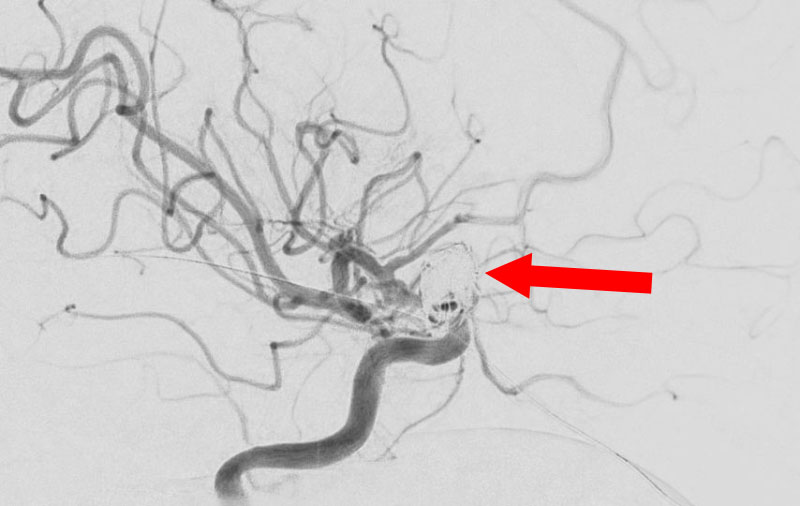

'25年10月

くも膜下出血

右前交通動脈瘤破裂

60代

救急外来

No.1587 手術前

No.1587 手術中

No.1587 手術後